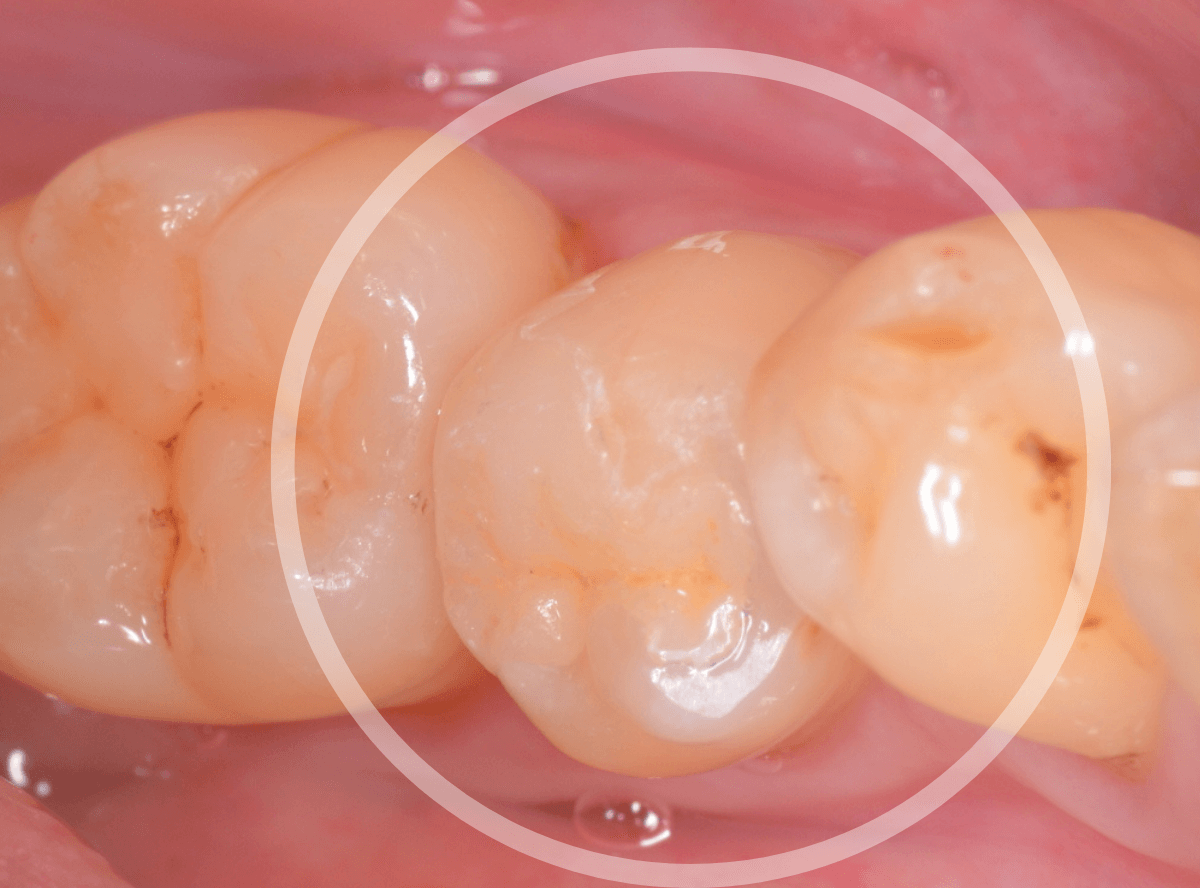

舌のそばの虫歯とセラミック治療

下の奥歯が虫歯になった患者さんのケースです。

〇部が虫歯の部分です。

写真で見てわかるように、常に舌が歯に触っているような状況です。

このような場合、虫歯を見つけづらいですし、治療の難易度もあがります。

虫歯治療後、特に症状もなく経過観察できましたので、つめものを作る治療に入ります。

セラミック治療をご希望されましたので、

小臼歯をE-MAX・インレー、

大臼歯をジルコニア・インレーで処置することになりました。

治療後の状態です。

自然な仕上がりで、患者さんにもご満足いただけました。

| 費用 | E-MAX・インレー (50,000円) ジルコニア・インレー (70,000円)x2 +保険治療費用(虫歯除去など) |

(2024年10月)